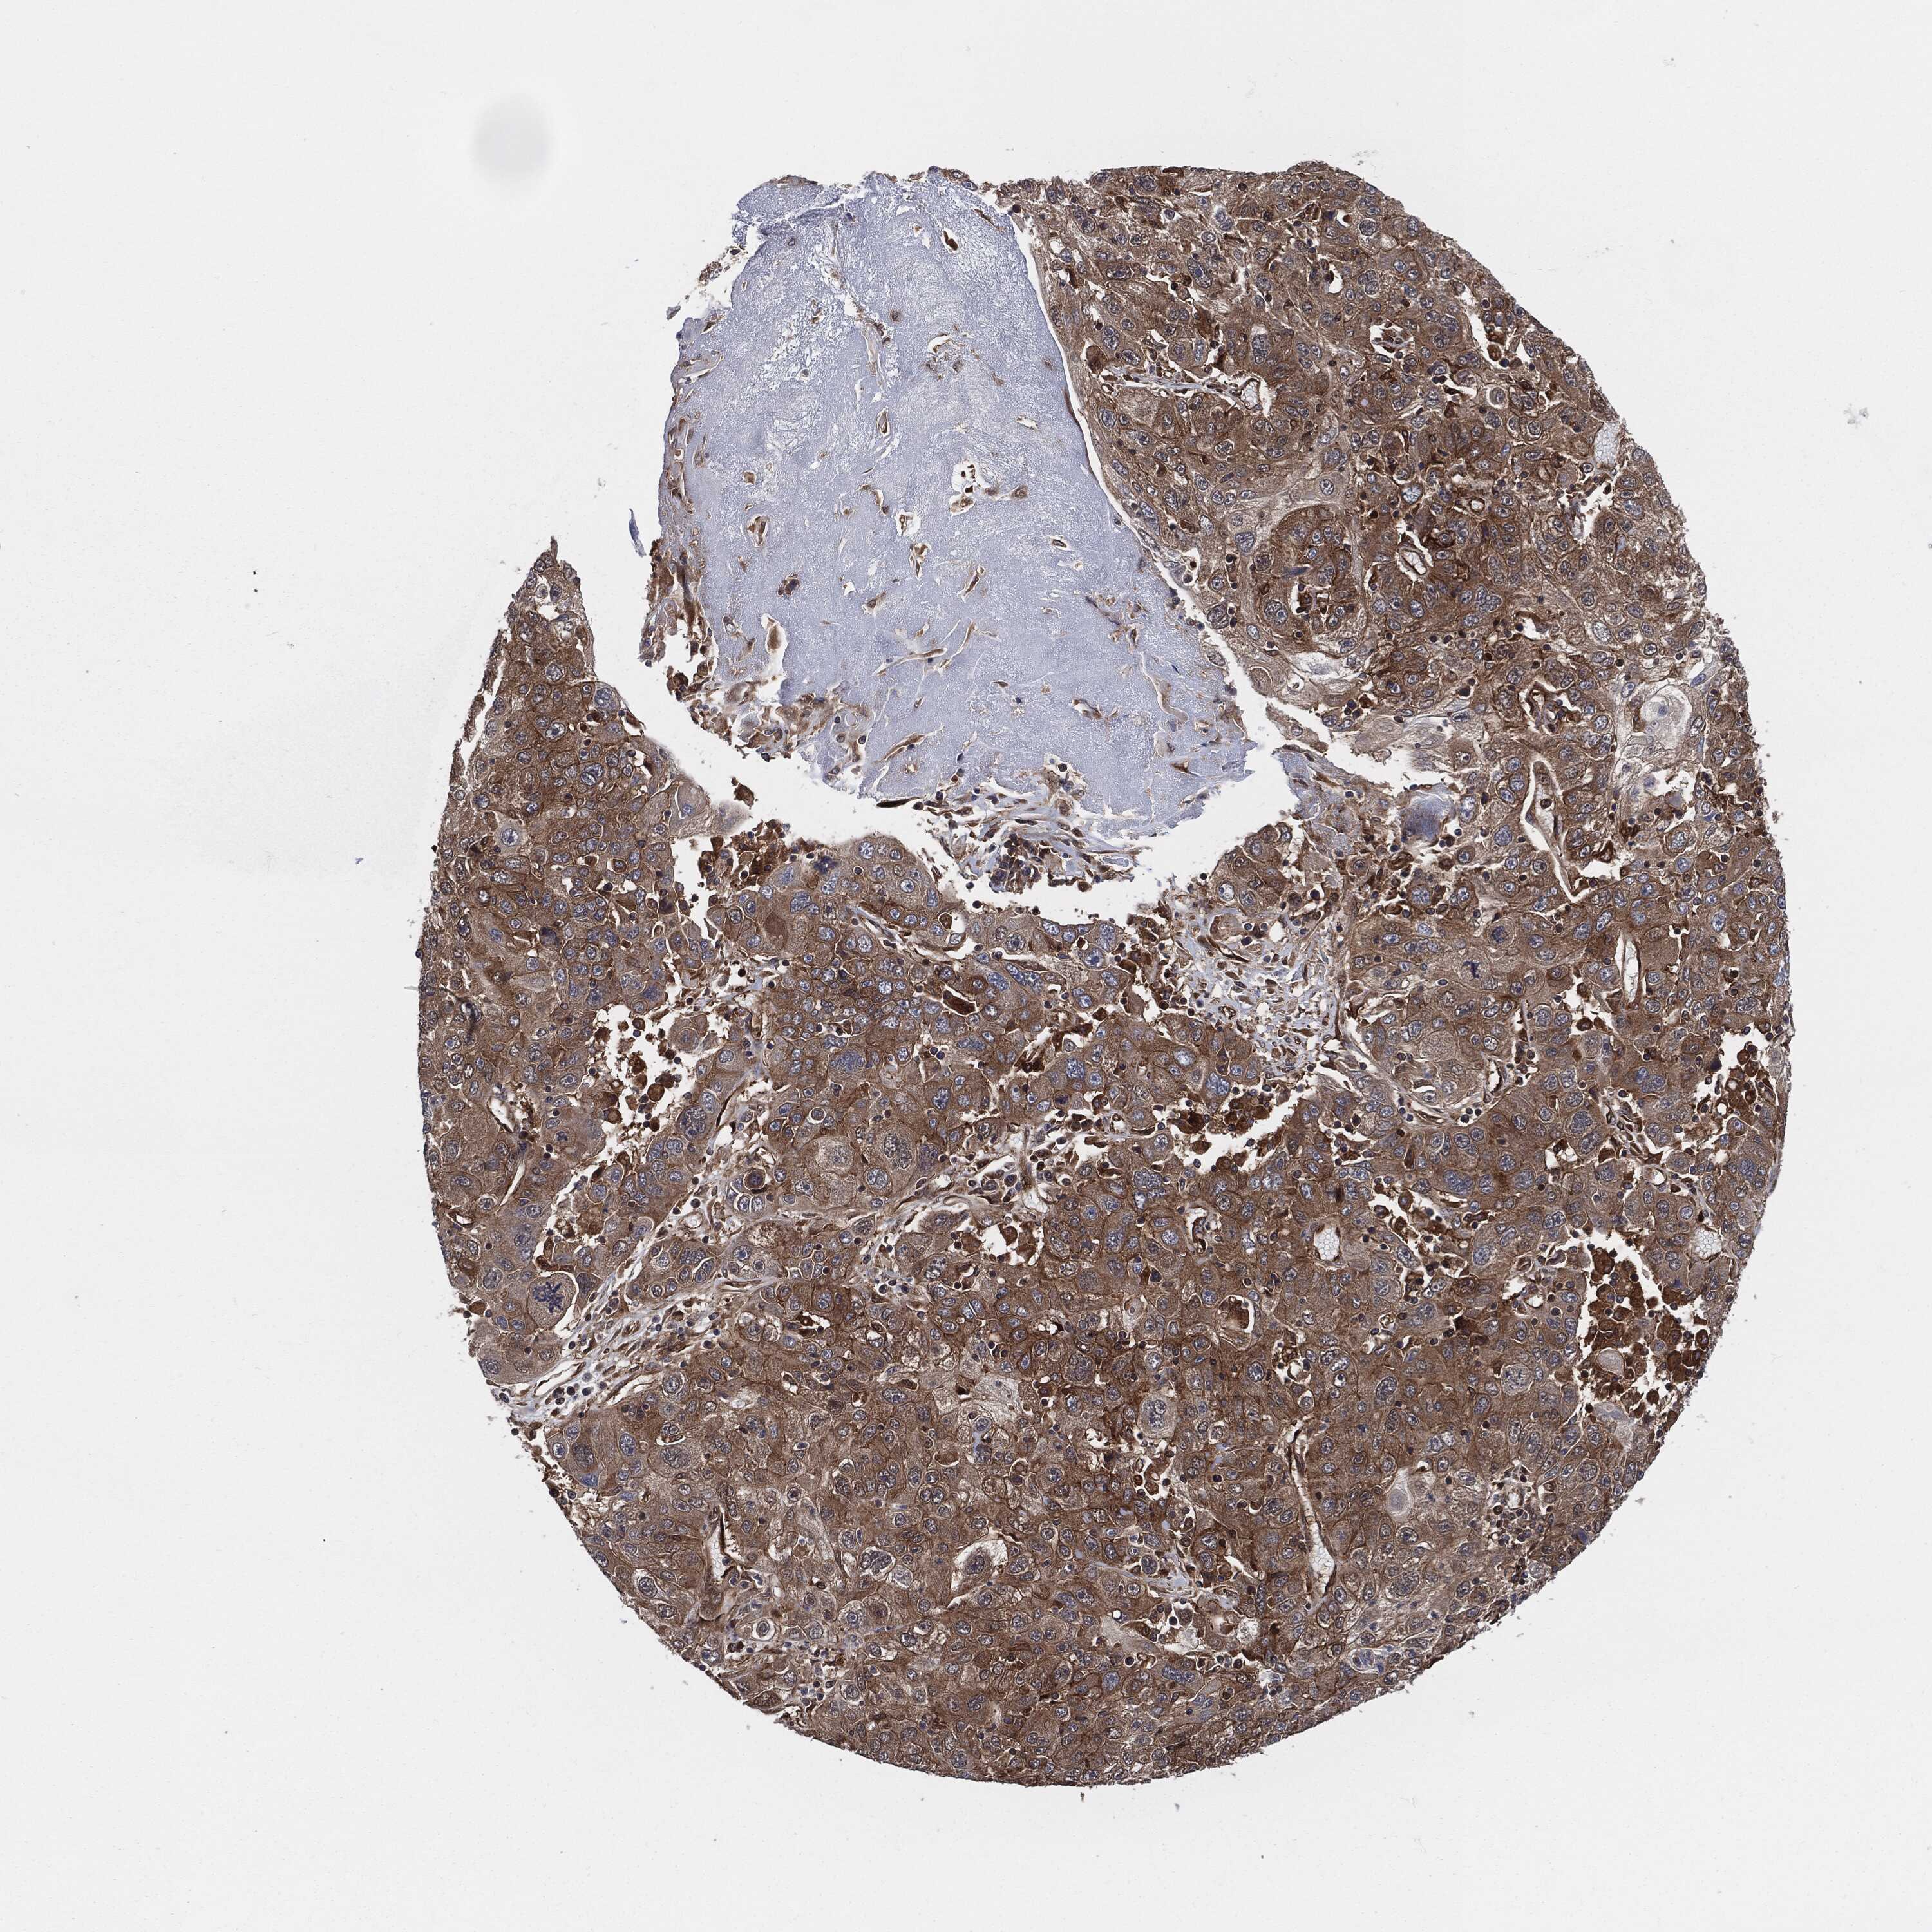

STOMACH CANCER - Protein expressioni

A mouse-over function shows sample information and annotation data. Click on an image to view it in a full screen mode. Samples can be filtered based on level of antibody staining by selecting one or several of the following categories: high, medium, low and not detected. The assay and annotation is described here.

Note that samples used for immunohistochemistry by the Human Protein Atlas do not correspond to samples in the TCGA dataset.

Antibody stainingi

Antibody staining in the annotated cell types in the current human tissue is reported as not detected, low, medium, or high, based on conventional immunohistochemistry profiling in selected tissues. This score is based on the combination of the staining intensity and fraction of stained cells.

Each image is clickable and will lead to virtual microscopy that enables deeper exploration of all samples and also displays staining intensity scores, fraction scores and subcellular localization as well as patient and tissue information for each sample.

HPA030419

HPA030420

HPA030422

CAB025196

CAB080286

CAB080287

Staining

High

Medium

Low

Not detected

Intensity

Strong

Moderate

Weak

Negative

Quantity

>75%

75%-25%

<25%

None

Location

Nuclear

Cytoplasmic/membranous

Cytoplasmic/membranous,nuclear

Adenocarcinoma, NOS

Adenocarcinoma, High grade